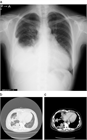

1. がん性胸膜炎に対する胸膜癒着療法のランダム化第3相試験:滅菌調整タルクvs. OK-432(WJOG8415L、J-PLEURA)の結果が世界肺癌学会(WCLC)2024で報告された。主要評価項目は胸膜癒着術30日後の胸水無再発割合であり、OK-432 43.9%、滅菌調整タルク 29.6% (p=0.9965)と有意差は認めなかった。

1. 癌性胸膜炎の症例に対する胸膜癒着術に使用する薬剤は、タルクが勧められる(推奨度1)

1. タルクの投与法としては、poudrageが推奨される(推奨度1)

1. ピシバニール等も使用されることがあるが、タルク以外の癒着剤の効果は同等である(推奨度2)